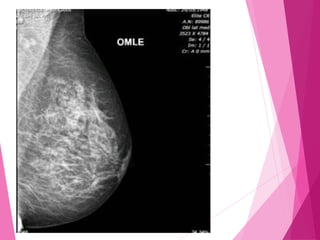

MÉDIO LATERAL OBLIQUA

Angular o mamógrafo de 35 à 45 graus, a

angulação depende do biótipo da paciente.

O feixe de raio será da região medial para

a lateral em obliqua.

A paciente deverá estar de frente para o

aparelho.

Elevar o braço para que o canto do bucky

esteja na região axilar, para que assim seja

visualizado o músculo peitoral.